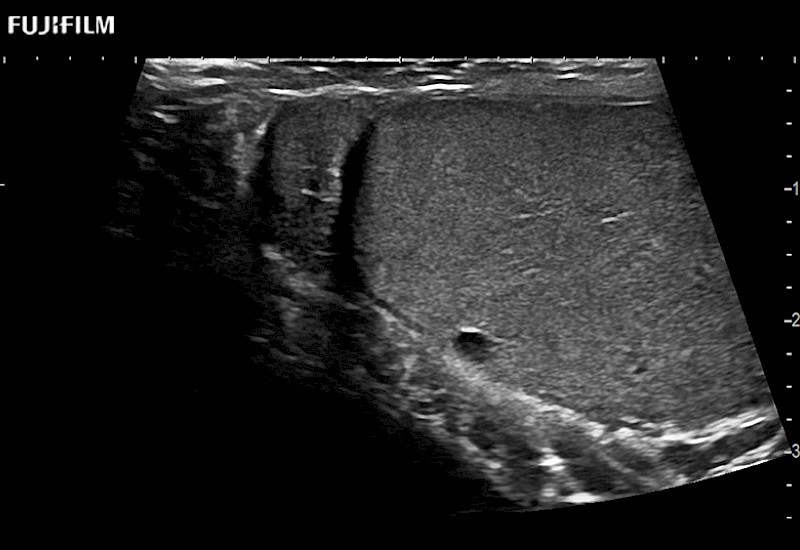

38mm footprint is ideal for scrotal and penile doppler imaging

Main Specifications:

Larger footprint is ideal for scrotal and penile doppler imaging

Designed for high-resolution imaging of the scrotal and penile regions. This advanced transducer offers exceptional image quality, user-friendly features, and specialized functionalities to support accurate urological diagnostics and enhance patient care.